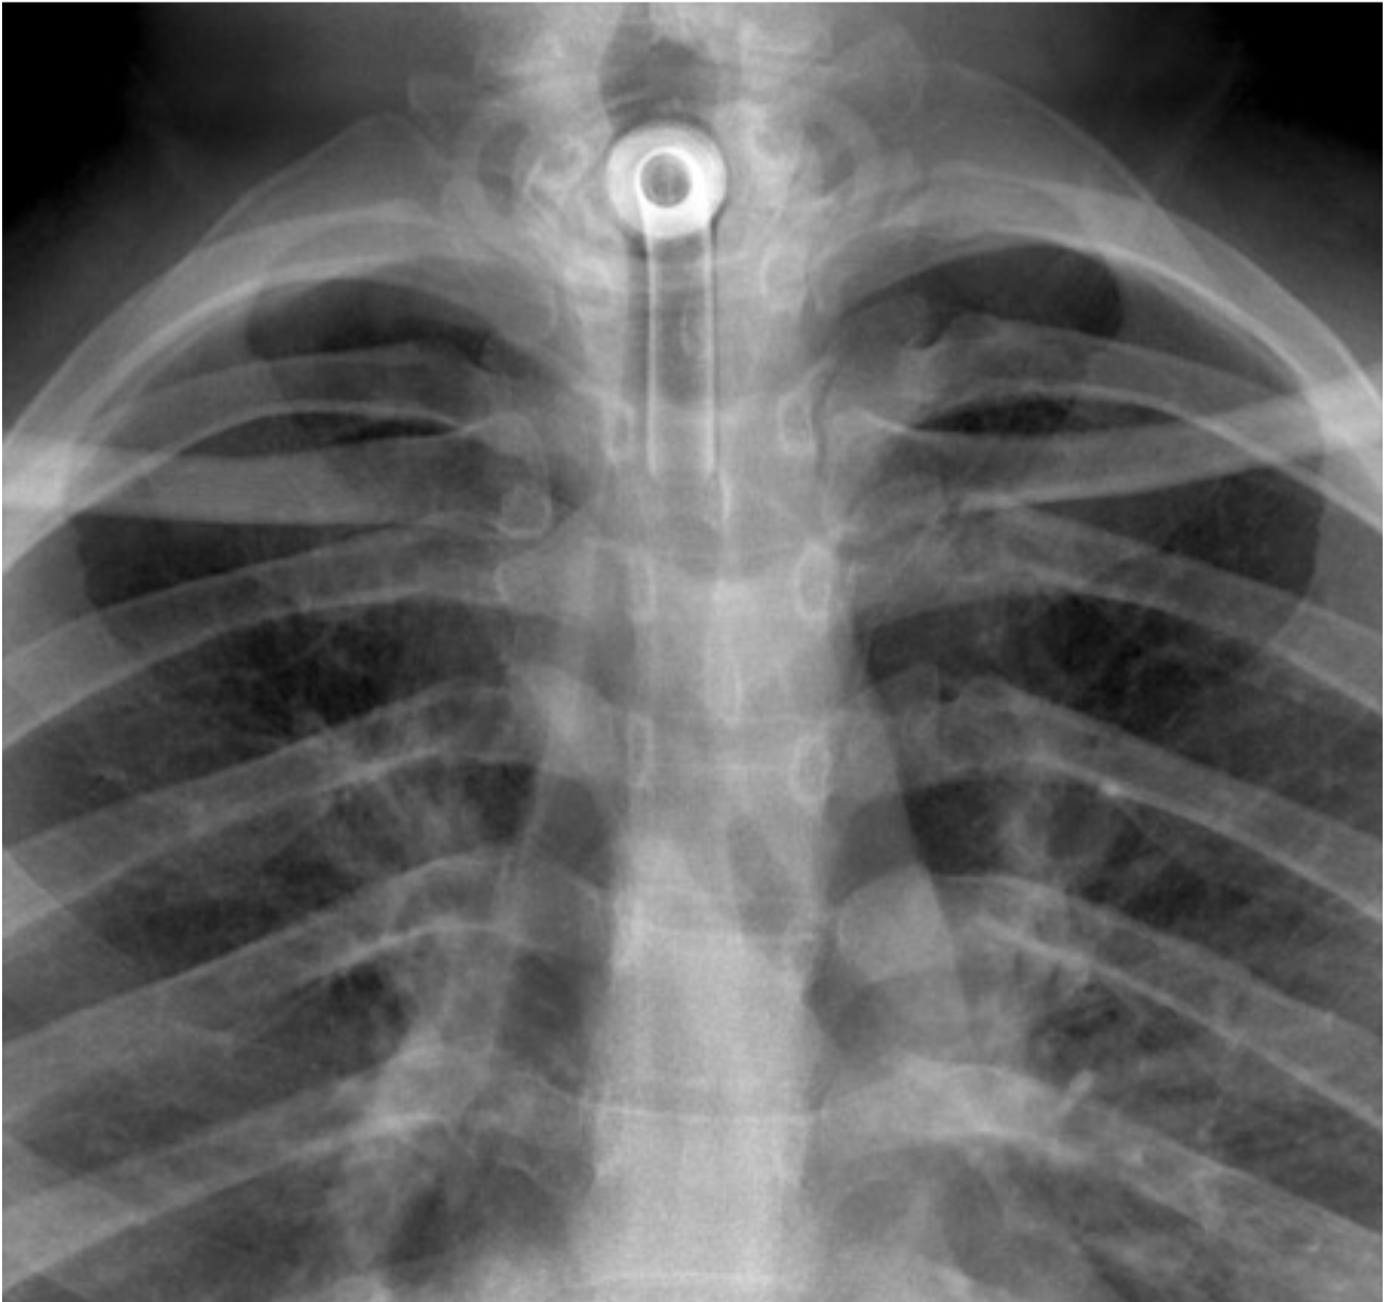

Example 3

Diagnosis

Endotracheal Tube